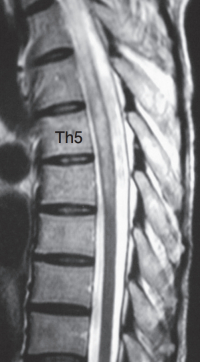

血液所見、血液生化学所見に異常を認めない。脳脊髄液所見は細胞数 69(多核球 60、単核球 9)/mm3(基準 0~2)、蛋白 62 mg/dL(基準 15~45)、糖62mg/dL。胸椎MRIのT2強調矢状断像と病変部の水平断像を別に示す。